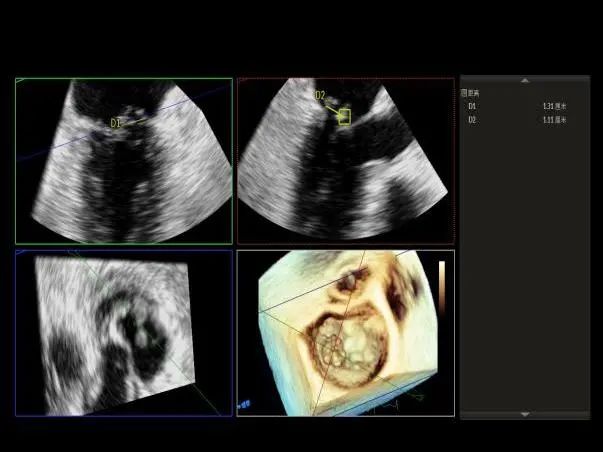

3D MV View:P1区瓣体瘤形成并中央型破裂孔,脱垂从P1到P2区,脱垂宽度13.1mm,破裂孔大小4.1×5.6mm